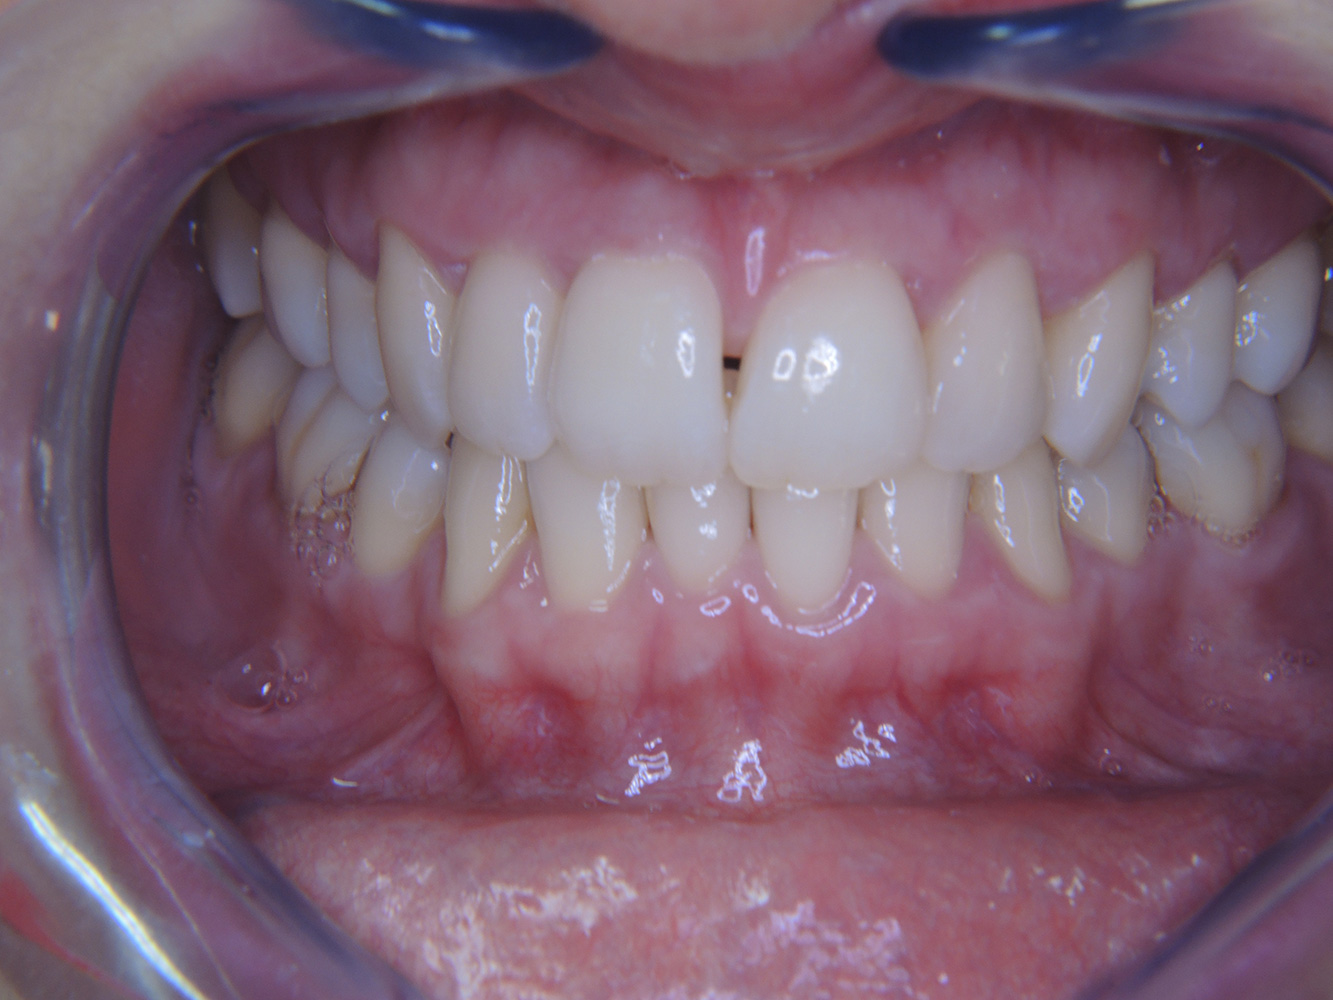

The diabetic patient with good oral health*

A 51-year old diabetic patient presents with good oral health at a prevention session. Her blood sugar levels are stable at HbA1c = 6.2%, and thus her condition is thought to be sufficiently managed with the antidiabetic drug metformin. The patient has no existing restorations or early oral disease. Using the dental results, it is possible to determine gingivitis in spite of an otherwise stable condition.

Despite the oral and general health parameters being stable, the patient’s underlying health condition requires her to attend a personalized prevention session. Diabetes mellitus is always associated with an increased risk of periodontitis (12). However, this can be controlled with good medicinal treatment. Regular monitoring of the HbA1c provides information about the course of the blood sugar level over the last eight to twelve weeks, with an HbA1c ≥ 6.5% indicating the presence of diabetes mellitus.

Because diabetes is so closely associated with periodontitis and has a significant impact on its development and progression, careful documentation is essential. Due to its significance, as described above, the patient should be asked for their current HbA1c value at every session.

The links between diabetes mellitus and the risk of periodontitis can be clearly explained during the consultation (12, 15), as can the impacts of a permanently elevated blood sugar level (hyperglycaemia) on the course and progression of periodontitis (16).

Even if the patient’s oral health gives no indication of any particular need for a shorter recall interval, twice-yearly prophylactic sessions are recommended due to the risks that come with diabetes mellitus and its association with an increased risk of periodontitis.